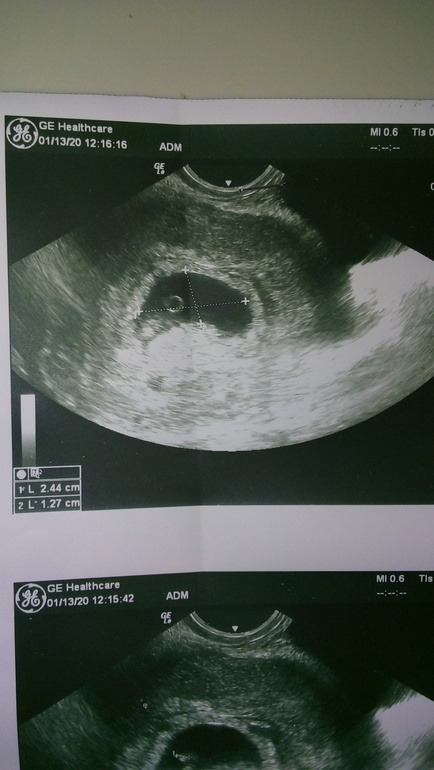

Тонус 5-6 недель УЗИ

Болит живот и поясница, тонус, треникиДевочки, привет! Помогите, может было подобное. Срок 5-6 недель, вчера стал сильно тянуть живот и поясницу. Сегодня на УЗИ сходила. Врач долго рассматривала, говорит не могу понять что за образование в матке😨 ( на фото под ПЯ) . потом сказала что это видимо матка так согнулась от тонуса, поставила угрозу, выписала ношпу и дюфастон. Ктр 3 мм, сб +. Так вот что то мне не дают покоя ее слова про новообразование, вдруг это не тонус 😢. У кого как тонус на УЗИ проявлялся?